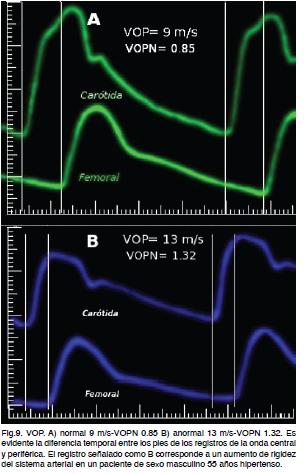

El tiempo transcurrido se mide entre el pie de las ondas de pulso carotideo y femoral promediando 10 latidos sucesivos. La velocidad se obtiene del cociente entre la distancia recorrida y el tiempo transcurrido (VOP). El valor obtenido es normalizado, velocidad de la onda de pulso normalizada (VOPN) de tal forma que valores de VOPN mayores a 1 son anormales indicando aumento de la rigidez del sistema arterial (Figura 9).